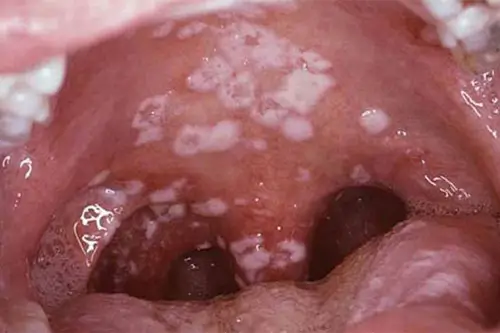

Ngoài những hình ảnh bệnh lậu ở nam giới, hình ảnh bệnh lậu ở nữ giới tại vùng kín như trên, người bệnh cũng có thể phát hiện thấy các hình ảnh bệnh lậu ở họng, miệng. Dấu hiệu bệnh lậu miệng hình thành khi bệnh nhân đã có quan hệ tình dục với người mắc lậu bằng đường miệng, hoặc ít gặp hơn là trường hợp sử dụng chung đồ cá nhân và bị nhiễm bệnh. Cụ thể, bệnh lậu ở miệng, lưỡi, họng sẽ được nhận biết qua các vấn đề bất thường gồm: